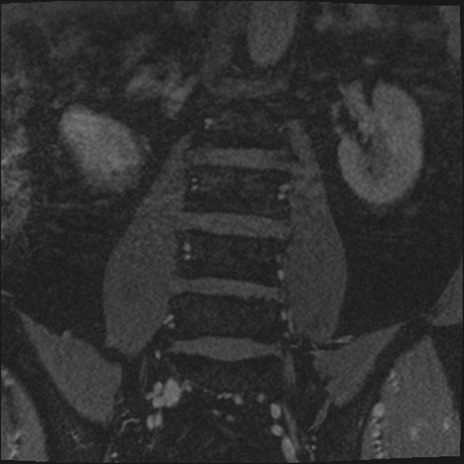

【整形】TIPS症例2 腰椎MRI 3D(冠状断像)

【症例】70歳代男性

【主訴】左下肢痛

【現病歴】2週間前くらいから腰痛、左下肢痛あり。左臀部から大腿、下腿外側のしびれが常時ある。歩行とともに同部位の痛みあり。

【身体所見】Lasegue70-/60+、Bragard-/±、PTR ±/±、ATR -/-、IP 5/5、TA 5/4、TS 5/5、EHL 右第1足趾なし/3、FHL 5/5、hypersthesia(-)、足背動脈触知良好

異常所見と診断は?